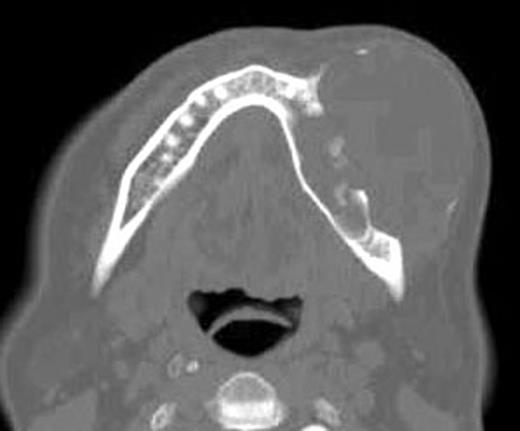

The panoramic radiography shows a large radiolucent and well-defined lesion with a radiopaque corticates margin involving the left mandibular premolar and molar (Fig. 2).

The panoramic radiography shows a large radiolucent and well-defined lesion with a radiopaque corticates margin involving the left mandibular premolar and molar area.